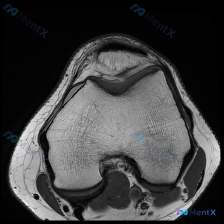

看到这个挺有代表性的病例,整理出来和大家分享一下思路。 病例基础信息 问题是:患者有膝前痛症状,临床怀疑软骨异常,提供了一张膝盖MRI-T1加权轴位图像,问图像里能看到什么病变。 影像读片结果 我们先看这张图像本身: 1. 扫描层面:膝关节上方,显示髌骨和股骨远端髌股关节面 2. 骨质结构:股骨远端...

刚看到这个病例,是临床怀疑膝关节软骨异常,只提供了一张膝关节髌股关节层面的轴位T1加权MRI,整理一下分析思路分享给大家。 一、病例与影像基本信息 本次仅提供单张膝关节MRI轴位T1序列影像,临床核心疑问是评估是否存在软骨异常,未提供患者病史、症状及其他临床资料,也未提供其他序列/切面的MRI影像。...

今天看到这个挺有讨论价值的读片问题,整理了完整信息和分析思路分享给大家。 病例/影像基本信息 这是一张膝关节轴位T1加权MRI图像,临床提出的问题是评估是否存在软骨异常。 我们先看这份影像的客观观察结果: 1. 整体解剖结构:髌骨、股骨远端滑车轮廓清晰,皮质骨光滑,无骨质破坏或骨皮质中断,骨髓信号大...

刚看到这个有意思的影像病例,整理一下完整资料和分析思路给大家参考。 病例基本信息 这是一张膝关节MRI T1加权轴位扫描影像,核心问题是:临床提示存在「软骨异常」,需要解读影像表现并分析原因。 影像客观评估结果 先给大家说客观的影像发现: 1. 骨性结构:股骨远端滑车、髌骨的骨皮质完整,松质骨髓信号...